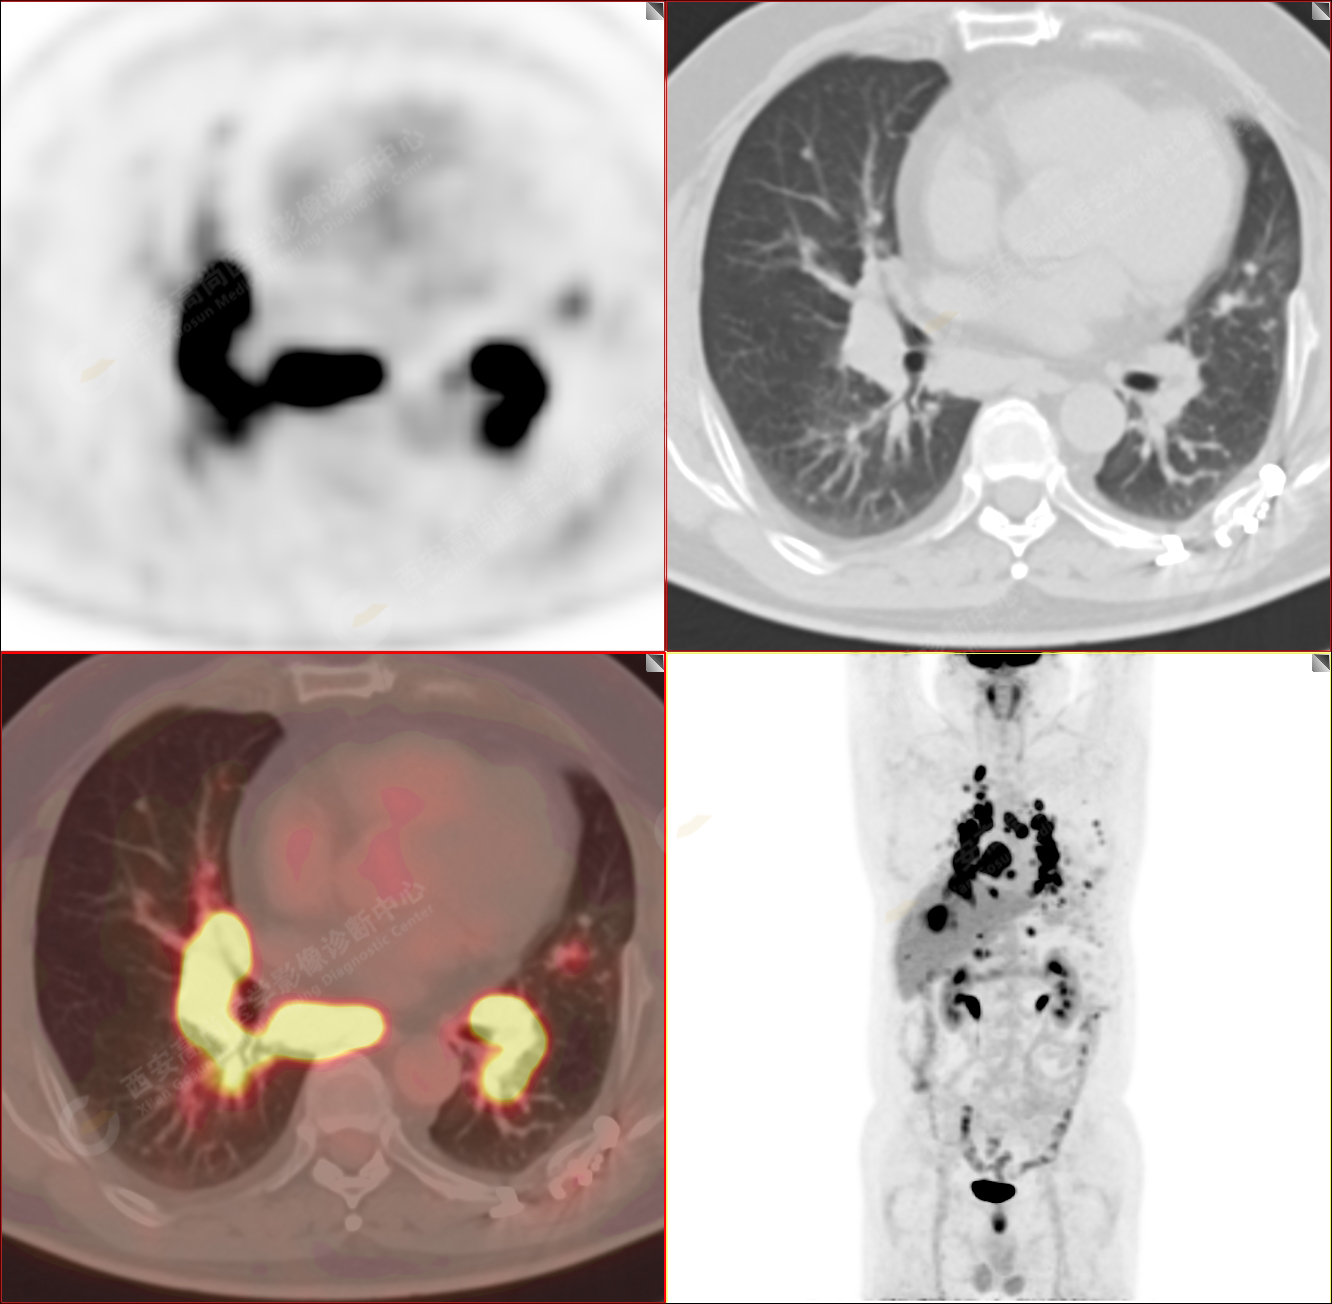

男性,53歲,頭暈半月入院,CT發(fā)現(xiàn)肺內(nèi)腫塊,雙肺多發(fā)大小不等實(shí)性及粟粒樣結(jié)節(jié),雙肺門(mén)及縱隔多發(fā)腫大淋巴結(jié)。病程中無(wú)發(fā)熱、胸悶氣及胸部不適。既往:左側(cè)肋骨外傷史。

PET/CT圖像